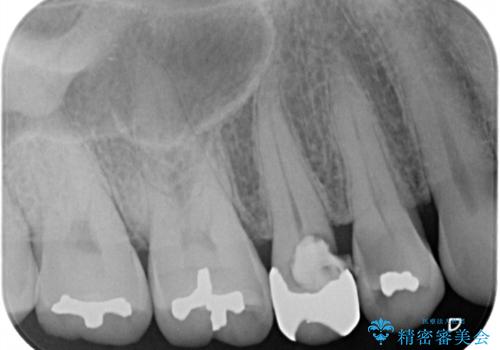

- 前歯のすきっぱを主訴にご来院された患者様です。他院でつめものやラミネートべニア(前歯の表面のみセラミックを貼り付ける)を行っていましたが、頻繁に外れることに悩まれており、クラウン(歯全体をセラミックがつつむ)をご希望されました。また、奥歯に大きな虫歯があり、歯が割れていたため、奥歯の治療も併せて行いました。

右上の歯に関しても、大きな虫歯があったため、前歯の経過観察の間に治療を行いました。